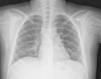

La radiografía de tórax inicial mostró infiltrado micronodular y reticular difuso con adenopatías hiliares bilaterales (fig. 1).

A su ingreso se detectó insuficiencia respiratoria crónica tipo I, sin repercusión cardiovascular, con hipoxemia, normocapnia e hiperlactatemia. La radiografía de tórax mostró infiltrado micronodular y reticular difuso con adenopatías hiliares bilaterales, concordante con el Estadio II de la clasificación de la American Thoracic Society para sarcoidosis torácica. Así mismo, la espirometría y la pletismografía reportaron una disminución de la relación VEF1/FVC, compatible con una neumopatía de patrón restrictivo leve como se ha descrito en las dos primeras etapas de la sarcoidosis pulmonar, que se normalizó después del tratamiento con prednisona.